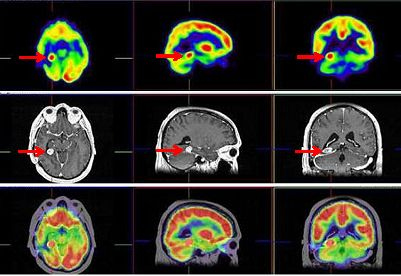

Nuevamente, en el seguimiento se detecta aumento de CEA (32,4 ng/ml), siendo el CT toráco-abdómino-pélvico normal. La RNM cerebral mostró una recidiva tumoral de 15 x 17 mm en lóbulo temporal derecho profundo (cuerpo-cola del hipocampo), junto al área de resección temporal previa. Se realiza estudio FDG PET-RNM cerebral (procedimientos separados con fusión posterior) que confirma la recidiva tumoral temporal derecha profunda (fig. 1).

La terapéutica tras el estudio PET-RNM cerebral consistió en radiocirugía, utilizando la Guía de Estereotaxia Brainlab, imágenes de fusión RNM-CT para planificación, fotones de 6 MV con técnica de arcoterapia dinámica conformada con un microcolimador multilámina Brainlab, administrando una dosis máxima de 22 Gy en la lesión temporal derecha, una dosis de 20 Gy al margen de la lesión, 0,8 Gy en las vías ópticas, 7 Gy en troncoencéfalo y 1,4 Gy en quiasma. La RNM cerebral de control mostró cambios postratamiento en la zona más caudal del lóbulo temporal derecho. Al cabo de 3 años, el paciente refiere cefalea aguda, discreta bradipsiquia y alteración de la marcha por hemiparesia izquierda. La RNM informa persistencia tumoral en región mesial posterior temporal derecha con infiltración en región más posterior del lóbulo temporal que afecta y atraviesa el tentorio, con compromiso del lóbulo cerebeloso derecho. Un estudio PET-RNM cerebral confirma la recurrencia tumoral (fig. 2).